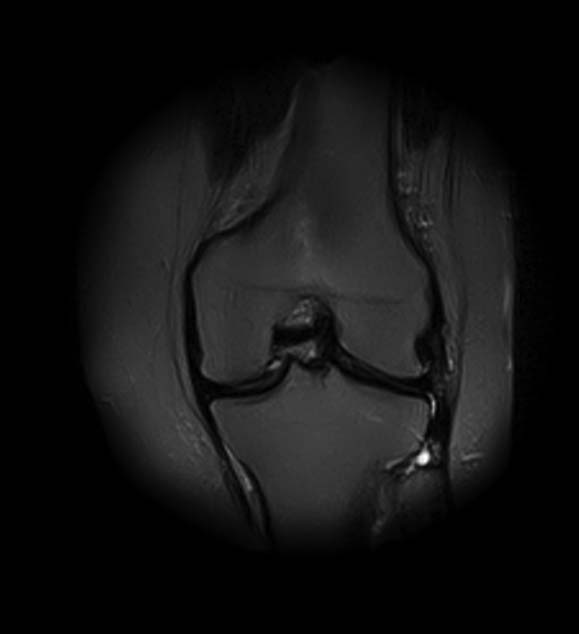

[Ortho] Показания для артроскопии

1. травма 5 лет назад - "ударилась коленом", с тех пор боли в суставе

3. стандартные рентгенограммы с небольшими изменениями - сужение

медиальной суставной щели

5. сустав клинически стабилен